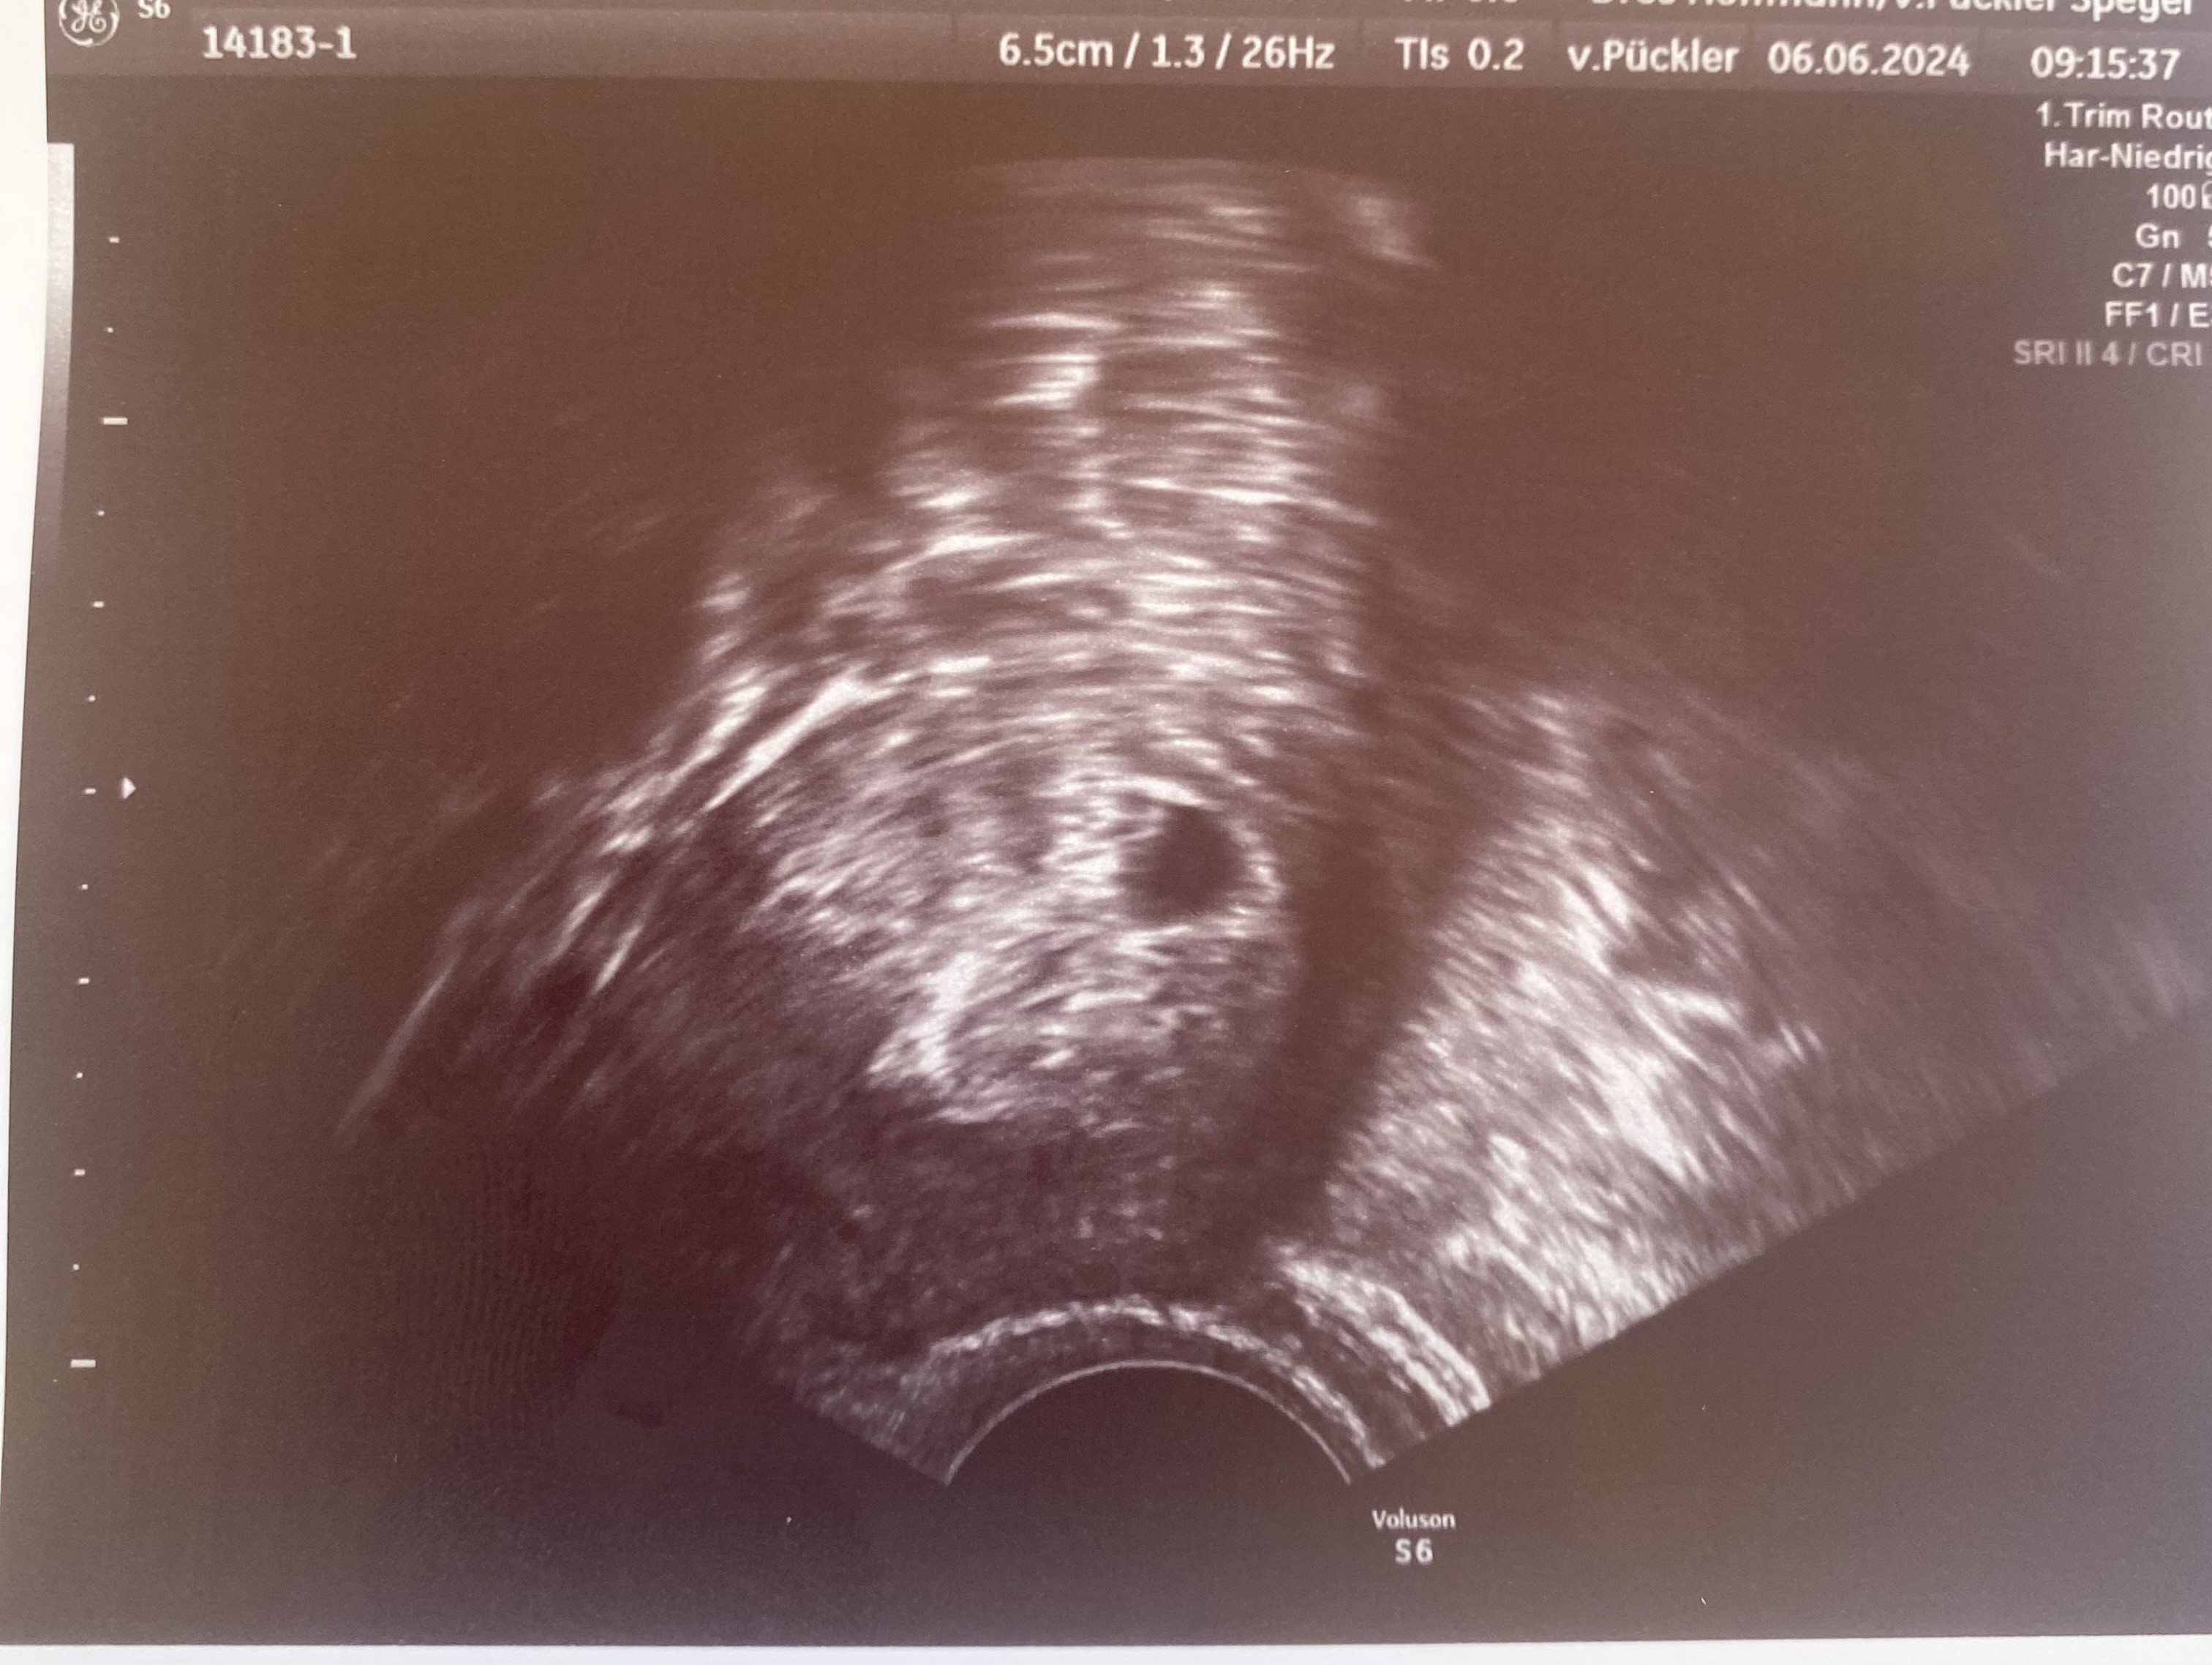

Tak czy inaczej jutro się wszystko wyjaśni. Bo będzie widać po wyniku i będę przynajmniej widziała co i jak. Ale spytam jeszcze Was czy robienie usg przez brzuch w takim stadium ma sens i jest normalne? Bo to mnie skłoniło do pójścia do innego lekarza.

Ja USG przez brzuch miałam robione dopiero podczas pierwszych badań prenatalnych